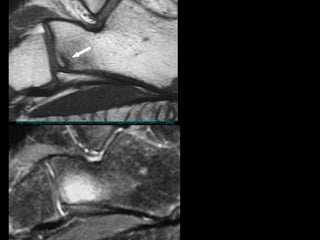

壓力性骨折 Stress Fracture 疲勞骨折 Fatigue fracture   骨質不良性骨折 Insufficiency fracture http://www.emedicine.com/radio/topic783.htm

the failure of the skeleton to withstand submaximal forces over time.  the failure of the skeleton to withstand submaximal forces over time.  http://www.mypacs.net/repos/mpv3_repo/viz/full/17093/854689.jpg